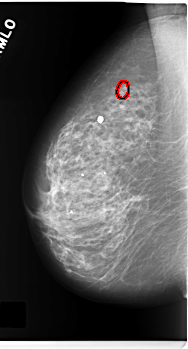

FILE: C_0171_1.RIGHT_MLO.OVERLAY

TOTAL_ABNORMALITIES 1

ABNORMALITY 1

LESION_TYPE CALCIFICATION TYPE PLEOMORPHIC DISTRIBUTION CLUSTERED

ASSESSMENT 4

SUBTLETY 4

PATHOLOGY MALIGNANT

TOTAL_OUTLINES 1

BOUNDARY